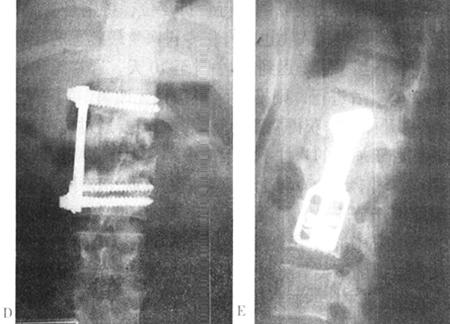

图13-55 22岁男性,L1爆裂骨折,后路CD固定,固定伤柱上二节和下一节